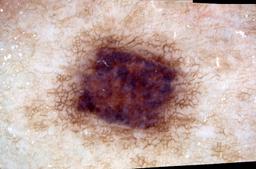

{

"age_approx": 15,

"anatom_site_general": "upper extremity",

"concomitant_biopsy": true,

"dermoscopic_type": "contact non-polarized",

"diagnosis_1": "Malignant",

"diagnosis_2": "Malignant melanocytic proliferations (Melanoma)",

"diagnosis_3": "Melanoma, NOS",

"diagnosis_confirm_type": "histopathology",

"image_type": "dermoscopic",

"lesion_id": "IL_5275237",

"melanocytic": true,

"patient_id": "IP_9529065",

"sex": "male"

}